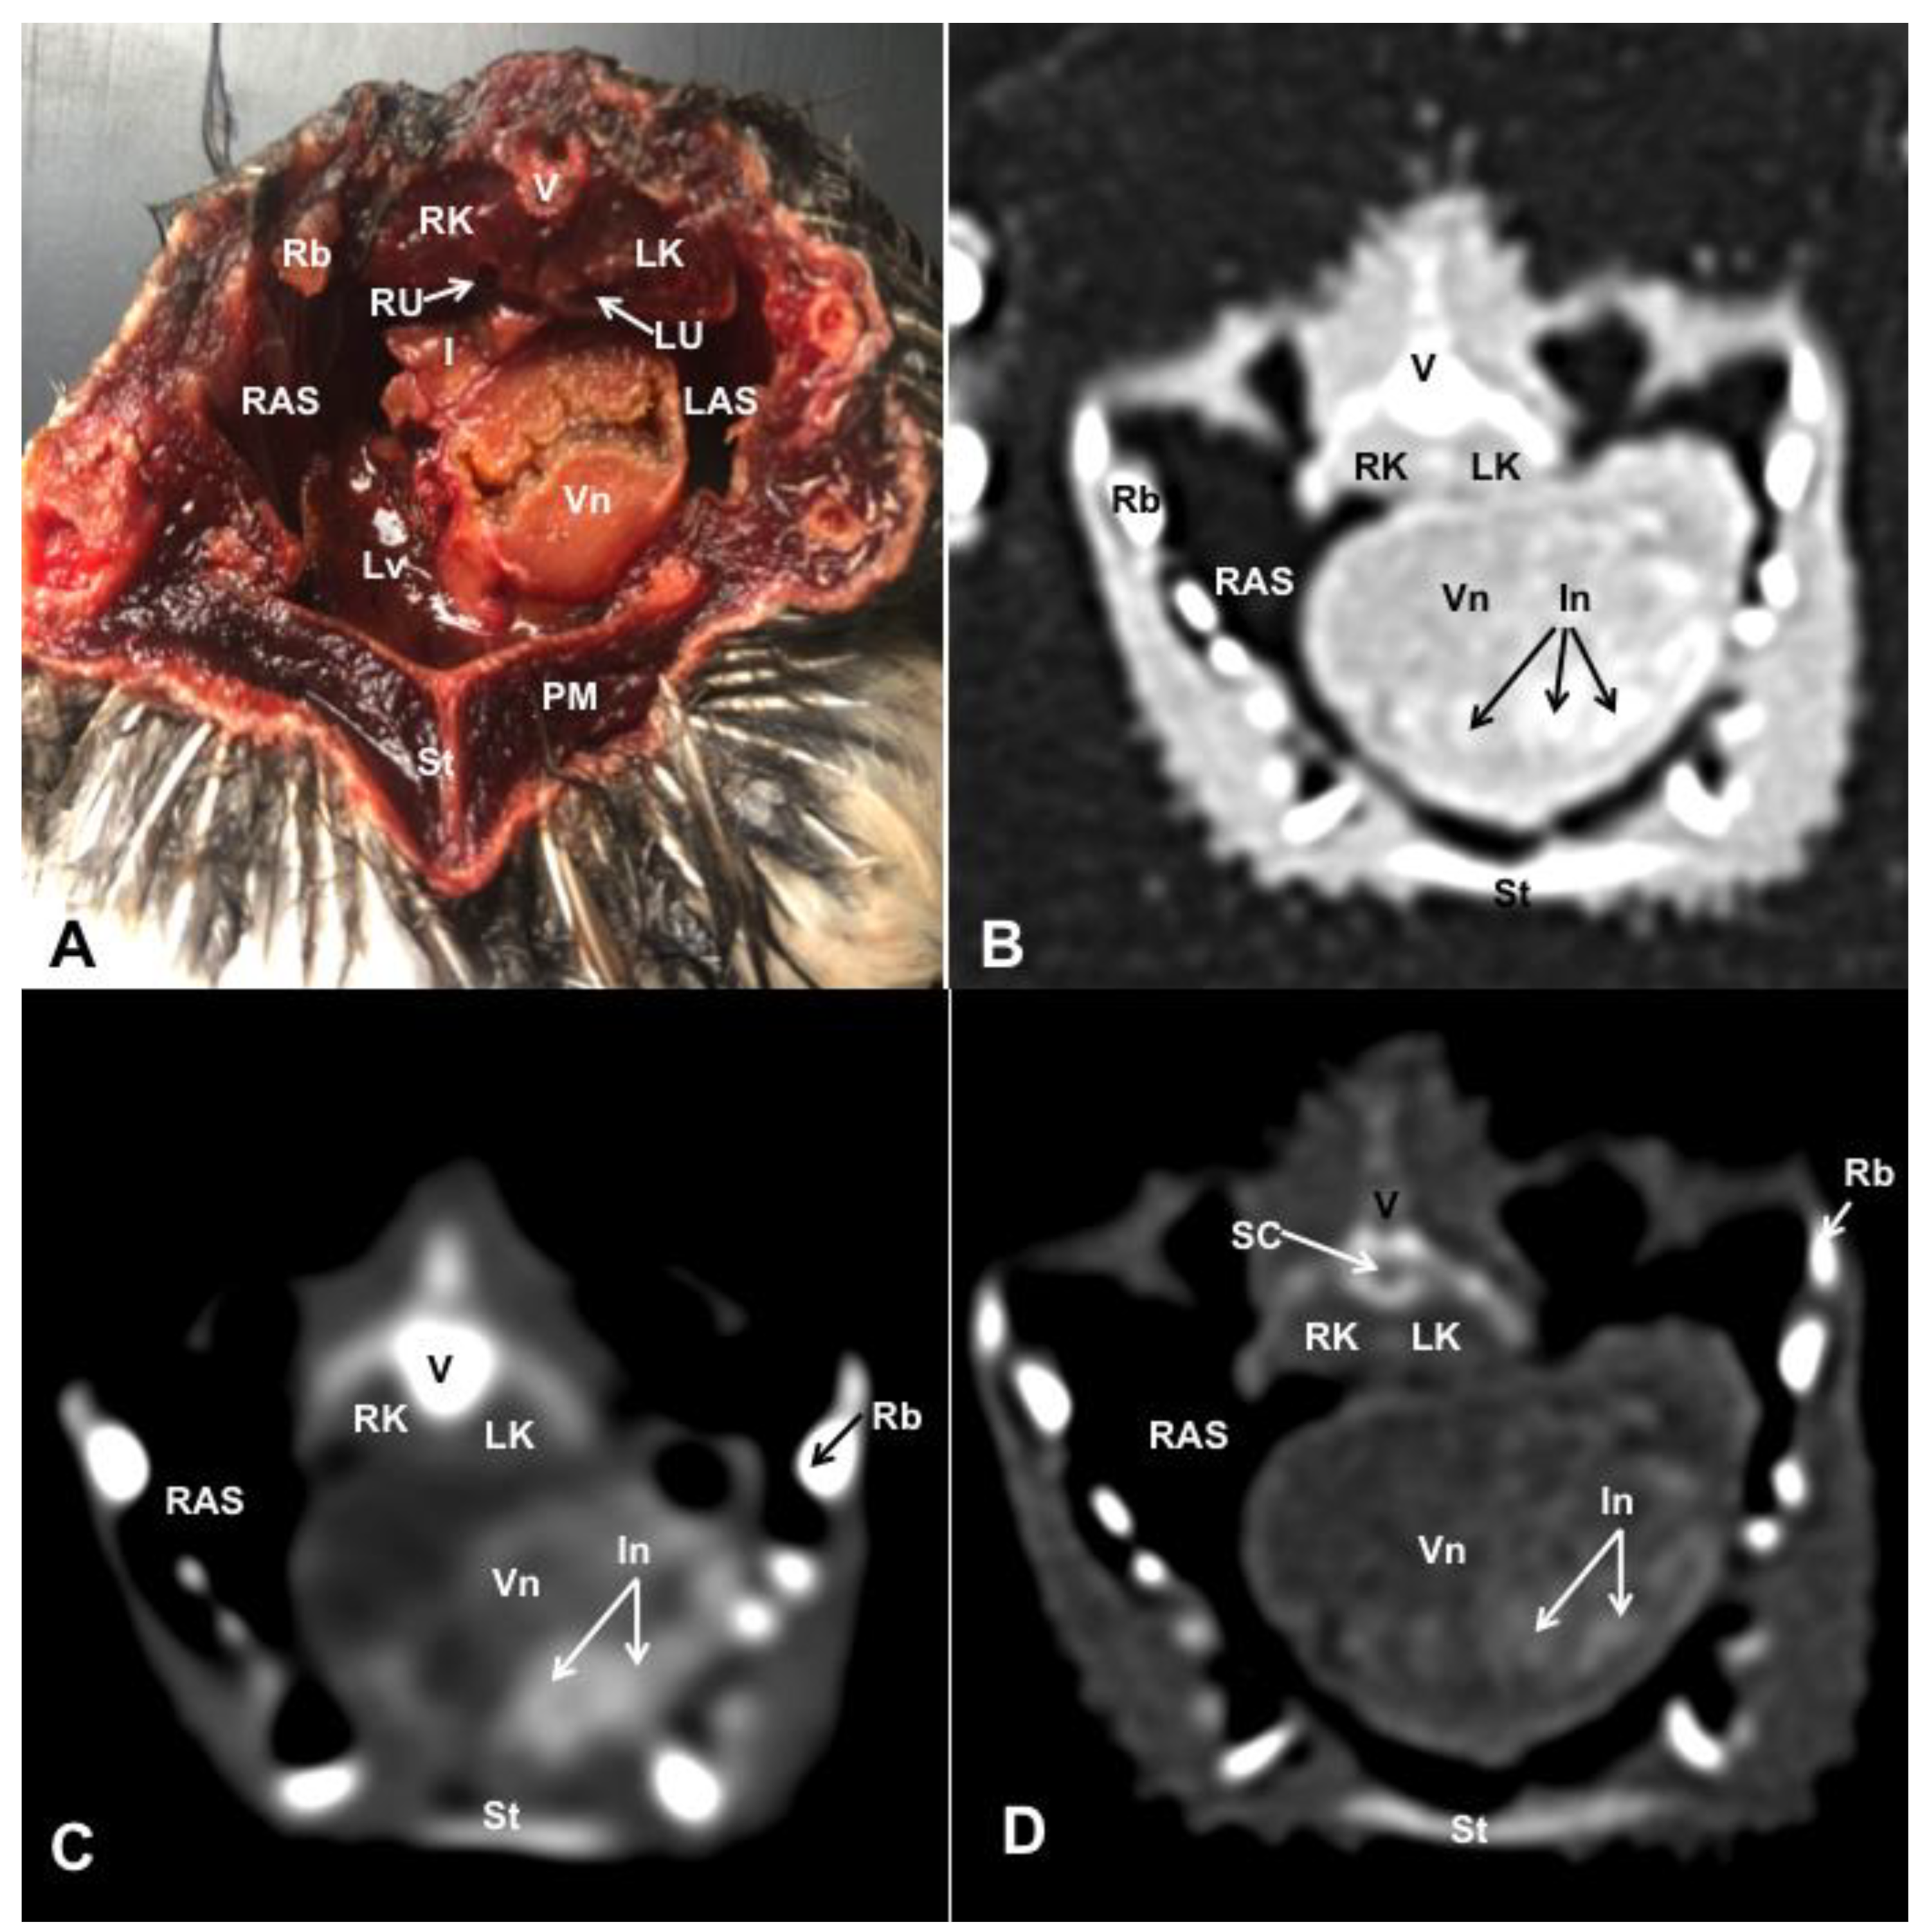

3.1. Anatomical Dissections and Cross-Sections

3.2. Computed Tomography Images